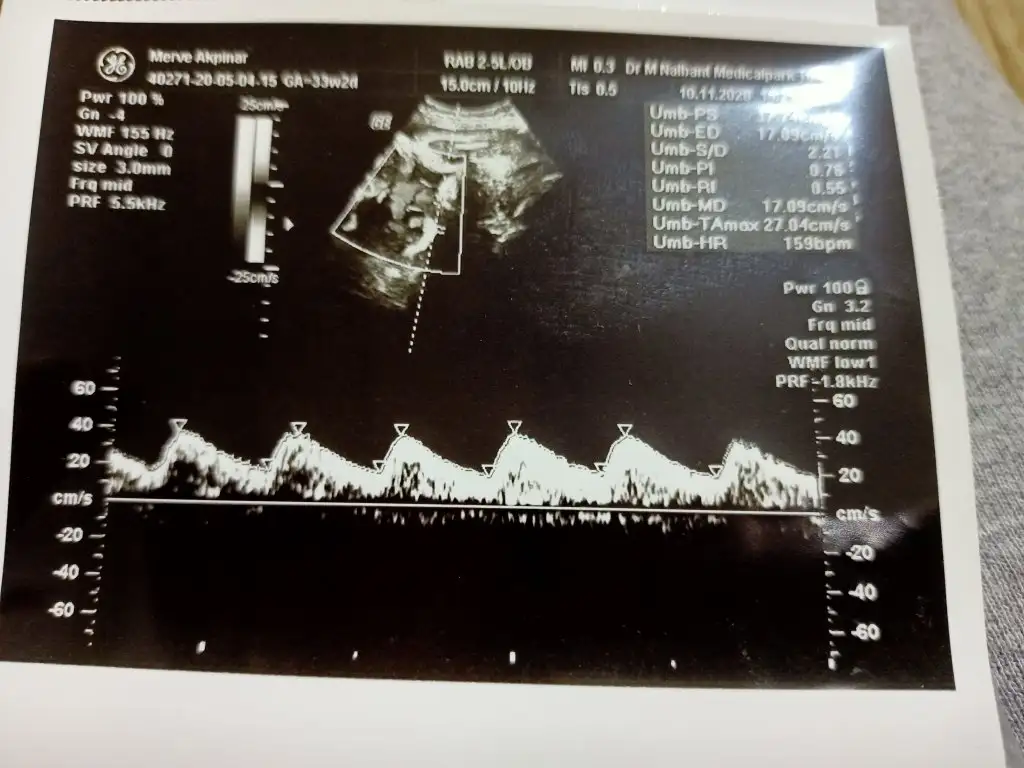

Canım çok şükür ki ilgili oluşun bak ortaya çıkarmış böyle bi riski, Allah korktuğumuza uğratmasın inşallah, sağlıkla kucağına alırsın erken de olsa kilosu az da olsa sorun değil doğduktan sonra toparlar yeter ki iyi olsun bebeğin kötü ihtimaller çok çok düşük bunları düşünüp daha çok tansiyonunu oynatma hiç. Allaha sığın dua et, olumlu düşün güzel olsun inşallahIlaç ve dozu konusunda şüphelenince başka bir doktora geldim öğleden sonra. Riskli gebelik konusunda bi arkadaş tavsiye etmişti. 30.Haftadan sonra doppler bakiliyomus bebekte. Bebeğin tansiyonunda bakiliyormus. Malesef bebegimin tansiyonu bozuk cıktıyeterli oksijen gitmiyor olabilir veya plesentada pıhtı olmuş olabilir dedi. Hastaneye yatırdı bizi ve bi doz daha ciğer geliştirici iğne vurdular. Eğer tansiyonu düzelmezse erken sezeryan olacak 35+0 Bugün sabah ki doktor 2500 ölçtü kilosunu öğleden sonraki 2350. Tansiyon bozukluğu beyin gelişimine zarar verebiliyormuş. O kadar moralim bozuldu ki. Hep gittiğim doktor hiç bundan bahsetmedi bilsem 30. Haftadan bu doktora gelirdim. Dualarınıza ihtiyacım var arkadaşlar annelik çok zormus ağlamaktan bi hal oldum.

Canım belki tansiyonu düzelir dua edelimIlaç ve dozu konusunda şüphelenince başka bir doktora geldim öğleden sonra. Riskli gebelik konusunda bi arkadaş tavsiye etmişti. 30.Haftadan sonra doppler bakiliyomus bebekte. Bebeğin tansiyonunda bakiliyormus. Malesef bebegimin tansiyonu bozuk cıktıyeterli oksijen gitmiyor olabilir veya plesentada pıhtı olmuş olabilir dedi. Hastaneye yatırdı bizi ve bi doz daha ciğer geliştirici iğne vurdular. Eğer tansiyonu düzelmezse erken sezeryan olacak 35+0 Bugün sabah ki doktor 2500 ölçtü kilosunu öğleden sonraki 2350. Tansiyon bozukluğu beyin gelişimine zarar verebiliyormuş. O kadar moralim bozuldu ki. Hep gittiğim doktor hiç bundan bahsetmedi bilsem 30. Haftadan bu doktora gelirdim. Dualarınıza ihtiyacım var arkadaşlar annelik çok zormus ağlamaktan bi hal oldum.

doppler bende de hiç bakılmadıDualarınız, iyi dilekleriniz ve desteğiniz için çok teşekkür ederim kızlar. Hiç tansiyon sorunum olmadı hamilelikte normalde de hep düşüktür benim 10-6 seyrederdi. Hamilelikte de 9-5 gitti. Çok şükür nst de kalp atışları normal o da cok onemli dedi doktor ama eğer tansiyonu düzelmezse çok bekletemicek. Benim endişem bikac hafta önce böyle bi sorun olup bebeğime zarar vermiş olma ihtimalidoktor 30. Haftadan sonra ölçülüyor doppler ile dedi ama hep gittiğim doktor ne ölçtü ne de bana bisey dedi. Daha bugün sabah suyu çok iyi coraspine devam dedi. Öğleden sonra geldiğim doktor bayağ tecrübeli ve yaşı da var suyu azalma eğiliminde dedi, coraspin maksimum 34. De kesilmeli yoksa kalbinde delik kapanmaz bebeğin dedi. Her bebekte oluyomuş ve ilk ağlamasa basınçla kapaniyomus o delik tek bir doktora güvenip beklememek lazım ki ben çok çeşitli doktora gittim yine de böyle oldu. Allah esirgesin yavrularımızı inşallah hepimiz sağlıkla kucagimiza alalım. Elimden geleni yaptım bu süreçte 8 aydır diyete sabretmek bile çok zordu ama bebeğime bisey olmasın diye dayandım. Son haftalarda böyle bi durumla karşılaşmak çok üzdü beni. Allah korusun inşallah

Kalp atışı bile dinlemiyoruz ölçümleri alıyor suyu iyi kg şu bu diyor yolluyorCanım kalp atışı gibi bir grafiği var ses olarakta kalp atımı duyuyorsun hatta ben sordum hu şekilde kalbine baktı diğer doktor diye ikisi farklıymış. Çünkü kordondan geçen kana her gittiğimde bakiliyo pihtidan dolayı onda da kalp atım sesi duyuluyo daha geniş aralıklı benzer bir grafikte. Bikac farklı damardan baktı hepsinde bozuk çıkınca yatırdı hastaneye. Belki doktorun bakmistir da dopler diye dememiştir sorun olmadığı için. Amin canım inşallah.

Benimki de hiç doppler bakmadı. Bi de tam mesajları okumadan yazmışım özür dilerim moralini daha da bozduysamCanım kalp atışı gibi bir grafiği var ses olarakta kalp atımı duyuyorsun hatta ben sordum hu şekilde kalbine baktı diğer doktor diye ikisi farklıymış. Çünkü kordondan geçen kana her gittiğimde bakiliyo pihtidan dolayı onda da kalp atım sesi duyuluyo daha geniş aralıklı benzer bir grafikte. Bikac farklı damardan baktı hepsinde bozuk çıkınca yatırdı hastaneye. Belki doktorun bakmistir da dopler diye dememiştir sorun olmadığı için. Amin canım inşallah.